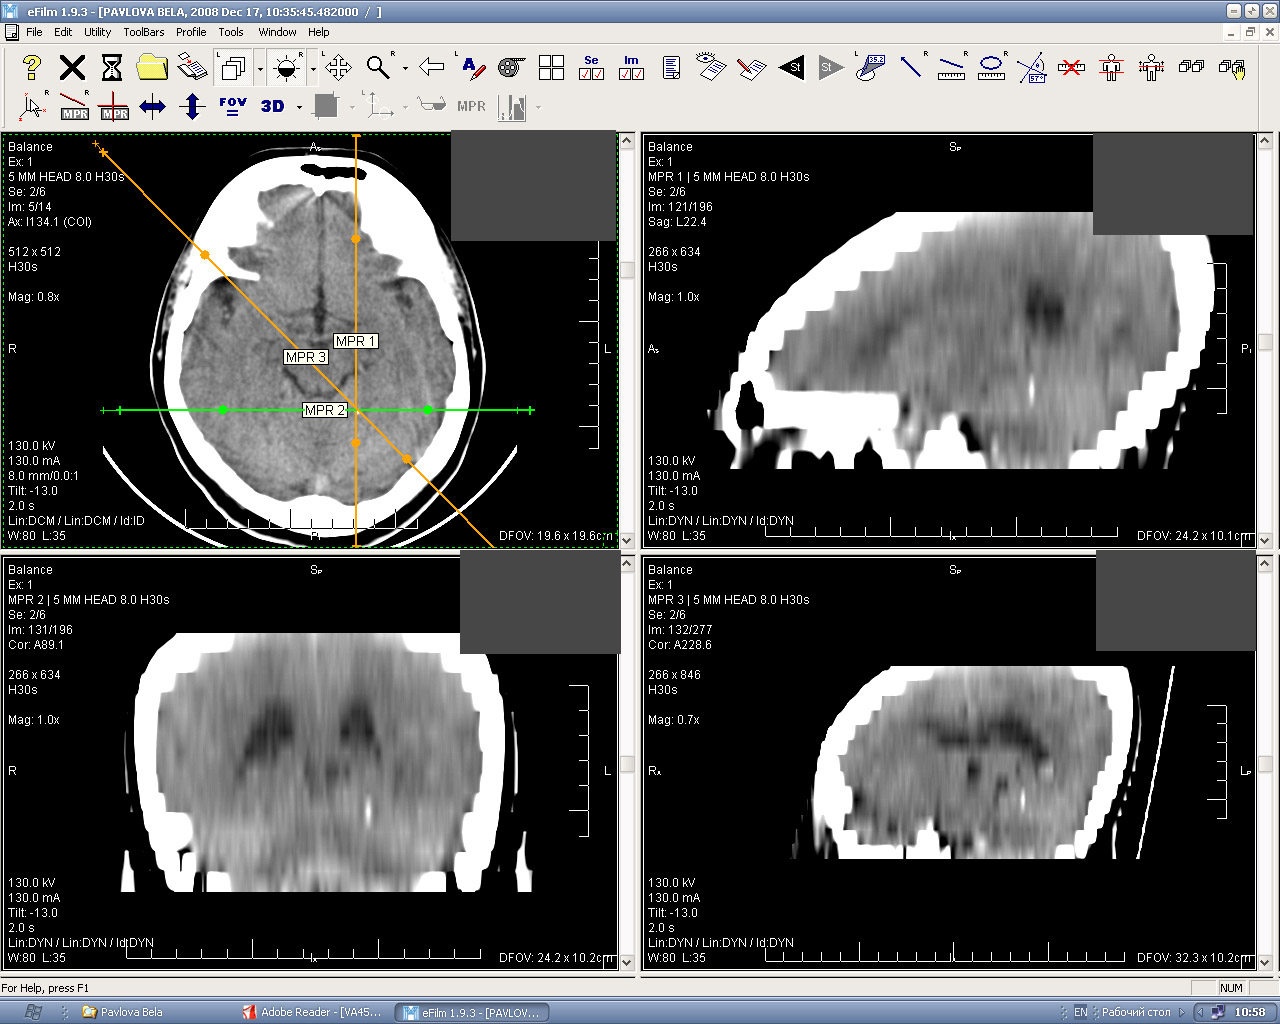

Лазерная камера сетевая для печати изображений на пленке стандарт dicom

/CMI%201000-640x500.jpg)